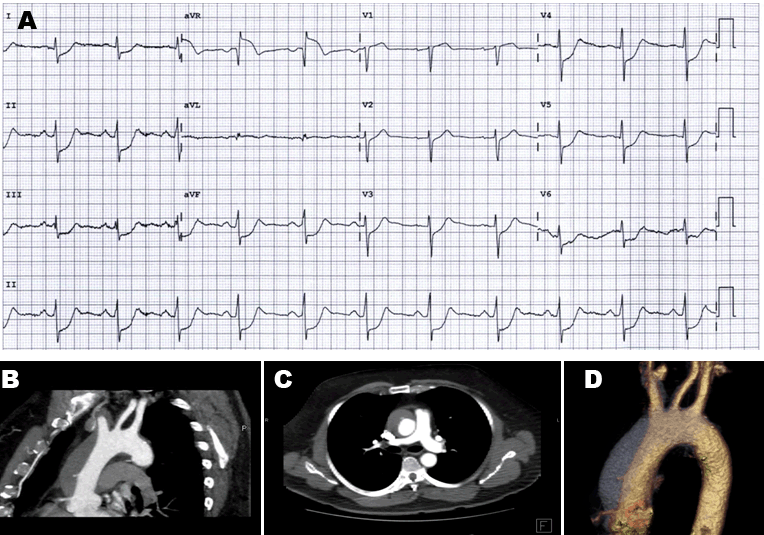

A previously healthy 77-year-old male, presenting with isolated sudden onset throat discomfort. He had no history of hypertension, relevant family history or other cardiovascular risk factors. Examination demonstrated bradycardia at a rate of 38 beats per minute with no radio-radial delay and although mildly hypertensive, there was no clinically significant brachial blood pressure difference. An ECG showed transient high grade atrioventricular block and serial troponins were within normal limits (Figure 1A). A transthoracic echocardiogram (TTE) was performed later that day which demonstrated a dilated 5.9 cm ascending aorta, subsequently an urgent computed tomography (CT) aortography revealed an extensive type a aortic dissection into the brachiocephalic, left common carotid and subclavian arteries in addition to bilateral external iliac, common iliac, and common femoral arteries. He progressed to acute aortic rupture and died as a result of hemorrhagic shock following the CT scan (Figure 1B).

Figure 1: (A) Electrocardiogram demonstrating high grade atrioventricular block, (B) Contrast-enhanced computed tomography demonstrating intimal flap, (C) Diagnostic of Stanford type A aortic dissection from the aortic root with extension into the supra-aortic vessels, and (D) 3D reconstructed images show the spiral false lumen in the descending aorta.